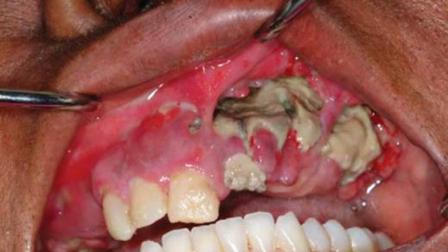

Esta sustancia causa graves daños a los adictos, pues destruye tejidos, con la consiguiente amputación de algunas partes del cuerpo donde se aplica la droga.

La DEA afirma que la desomorfina apareció internacionalmente en 2002 y describió sus efectos: “La piel, en abusadores de largo tiempo, puede presentarse como verdosa y escamosa debido a vasos sanguíneos dañados, trombosis y tejidos blandos deteriorados alrededor de los sitios de inyección.

La apariencia de la piel es similar al cuero rugoso y escamado de un cocodrilo. Las lesiones cutáneas pueden eventualmente transformarse en severo daño de tejidos que lleva a tromboflebitis y gangrena. Esta condición puede resultar en la amputación de miembros y a veces muerte.”

Un texto publicado por la Revista Médica Estadunidense consigna lo que el doctor Danny Thekkemuriyil relató: “Vimos que su dedo se cayó y vimos una úlcera que parecía muy severa y llagas en sus muslos, y realmente se ajustaba a la descripción de krokodil”.